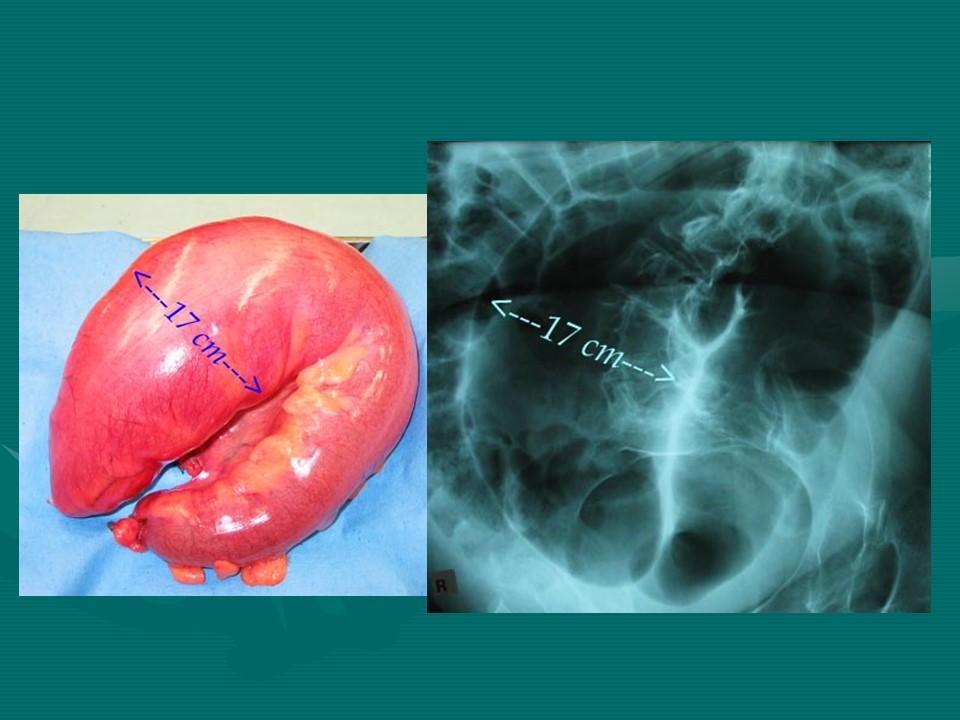

“肠梗阻的分类及影像诊断PPT” 的相关文章